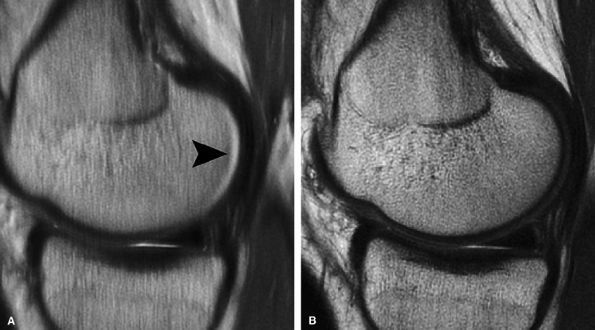

FIGURE 7.3 ● (A) Sagittal fast spin-echo MR image of the knee in a 39-year-old man performed on a high-field system (1.5 Tesla) demonstrates poor distinction between the subchondral plate and adjacent basilar components of cartilage at a TE of 110 msec (white arrow). (B) Corresponding image with all acquisition parameters held the same except for a moderate TE of 27.5 msec demonstrates improved cartilage–subchondral bone distinction (black arrow).